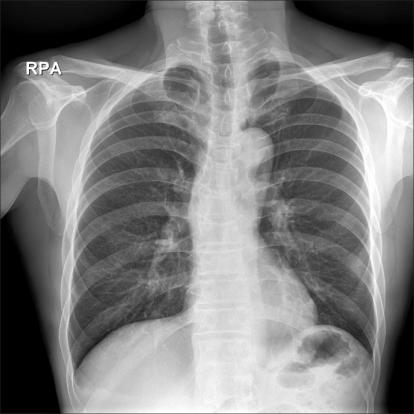

We experienced an extremely rare complication during performance of laparoscopic totally extraperitoneal (TEP) inguinal hernia repair for a 57-year-old healthy man. About 50 minutes after CO(2) insufflation, the patient developed tachycardia, hypoxemia, hypercapnia and an increased airway pressure. Right pneumothorax with subcutaneous emphysema was recognized on the emergency chest X-ray and this was successfully treated by chest tube insertion. Anesthesiologists should be aware of the possible occurrence of pneumothorax during laparoscopic TEP hernia repair.

我们在为一名 57 岁健康男性行腹腔镜完全腹膜外(TEP)腹股沟疝修补术中遇到了一种极其罕见的并发症。在二氧化碳充气约 50 分钟后,患者出现心动过速、低氧血症、高碳酸血症和气道压力升高。急诊胸片显示右侧气胸伴皮下气肿,经胸腔引流管插入成功治疗。麻醉师应意识到在腹腔镜 TEP 疝修补术中可能发生气胸。